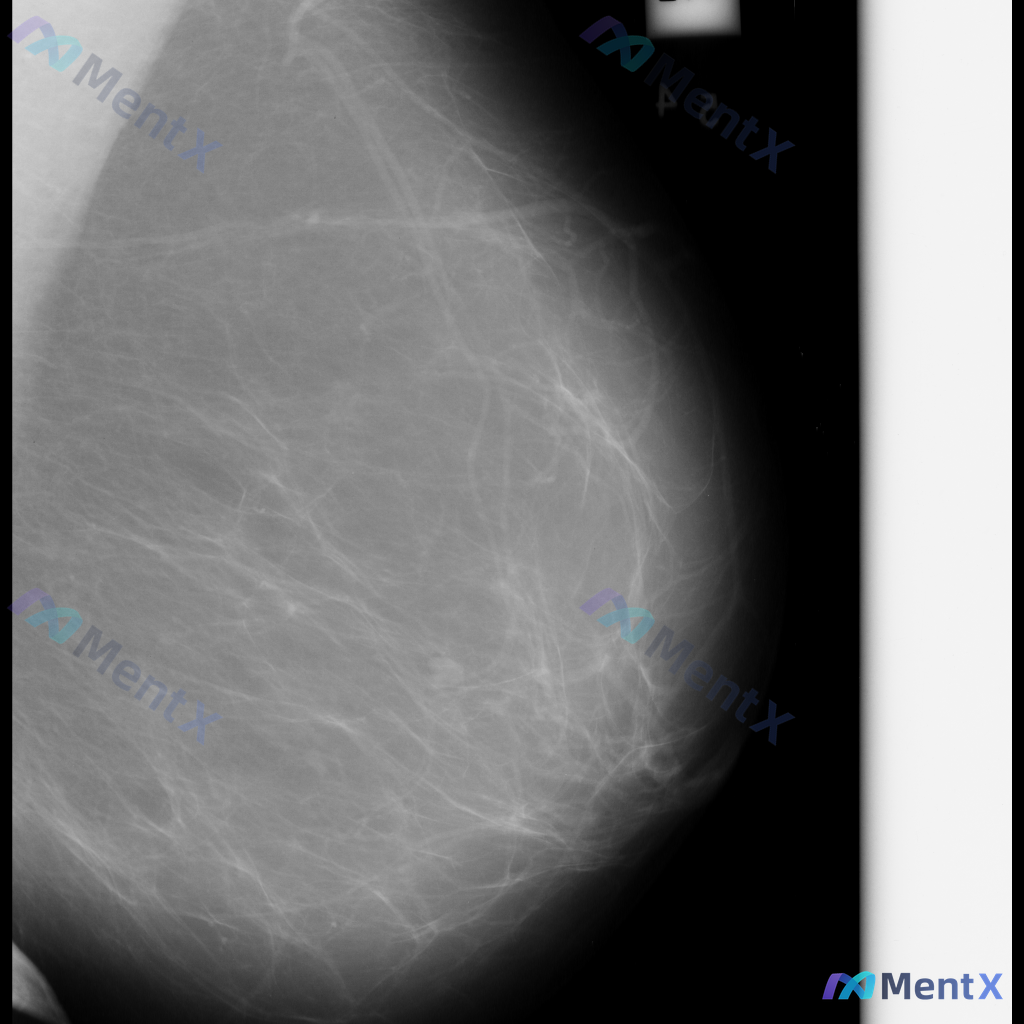

整理到一份单张乳腺钼靶影像的资料,分享给大家讨论: - 背景:乳腺整体为多量腺体型或致密型(BI-RADS C/D型可能) - 主要异常:在乳腺中下部略偏中央区域,可见局灶性不对称密度,或伴有轻度腺体结构紊乱 - 伴随征象:未见明确簇状/线样等可疑恶性钙化,无明确结构扭曲、皮肤增厚/回缩、乳头内陷等...